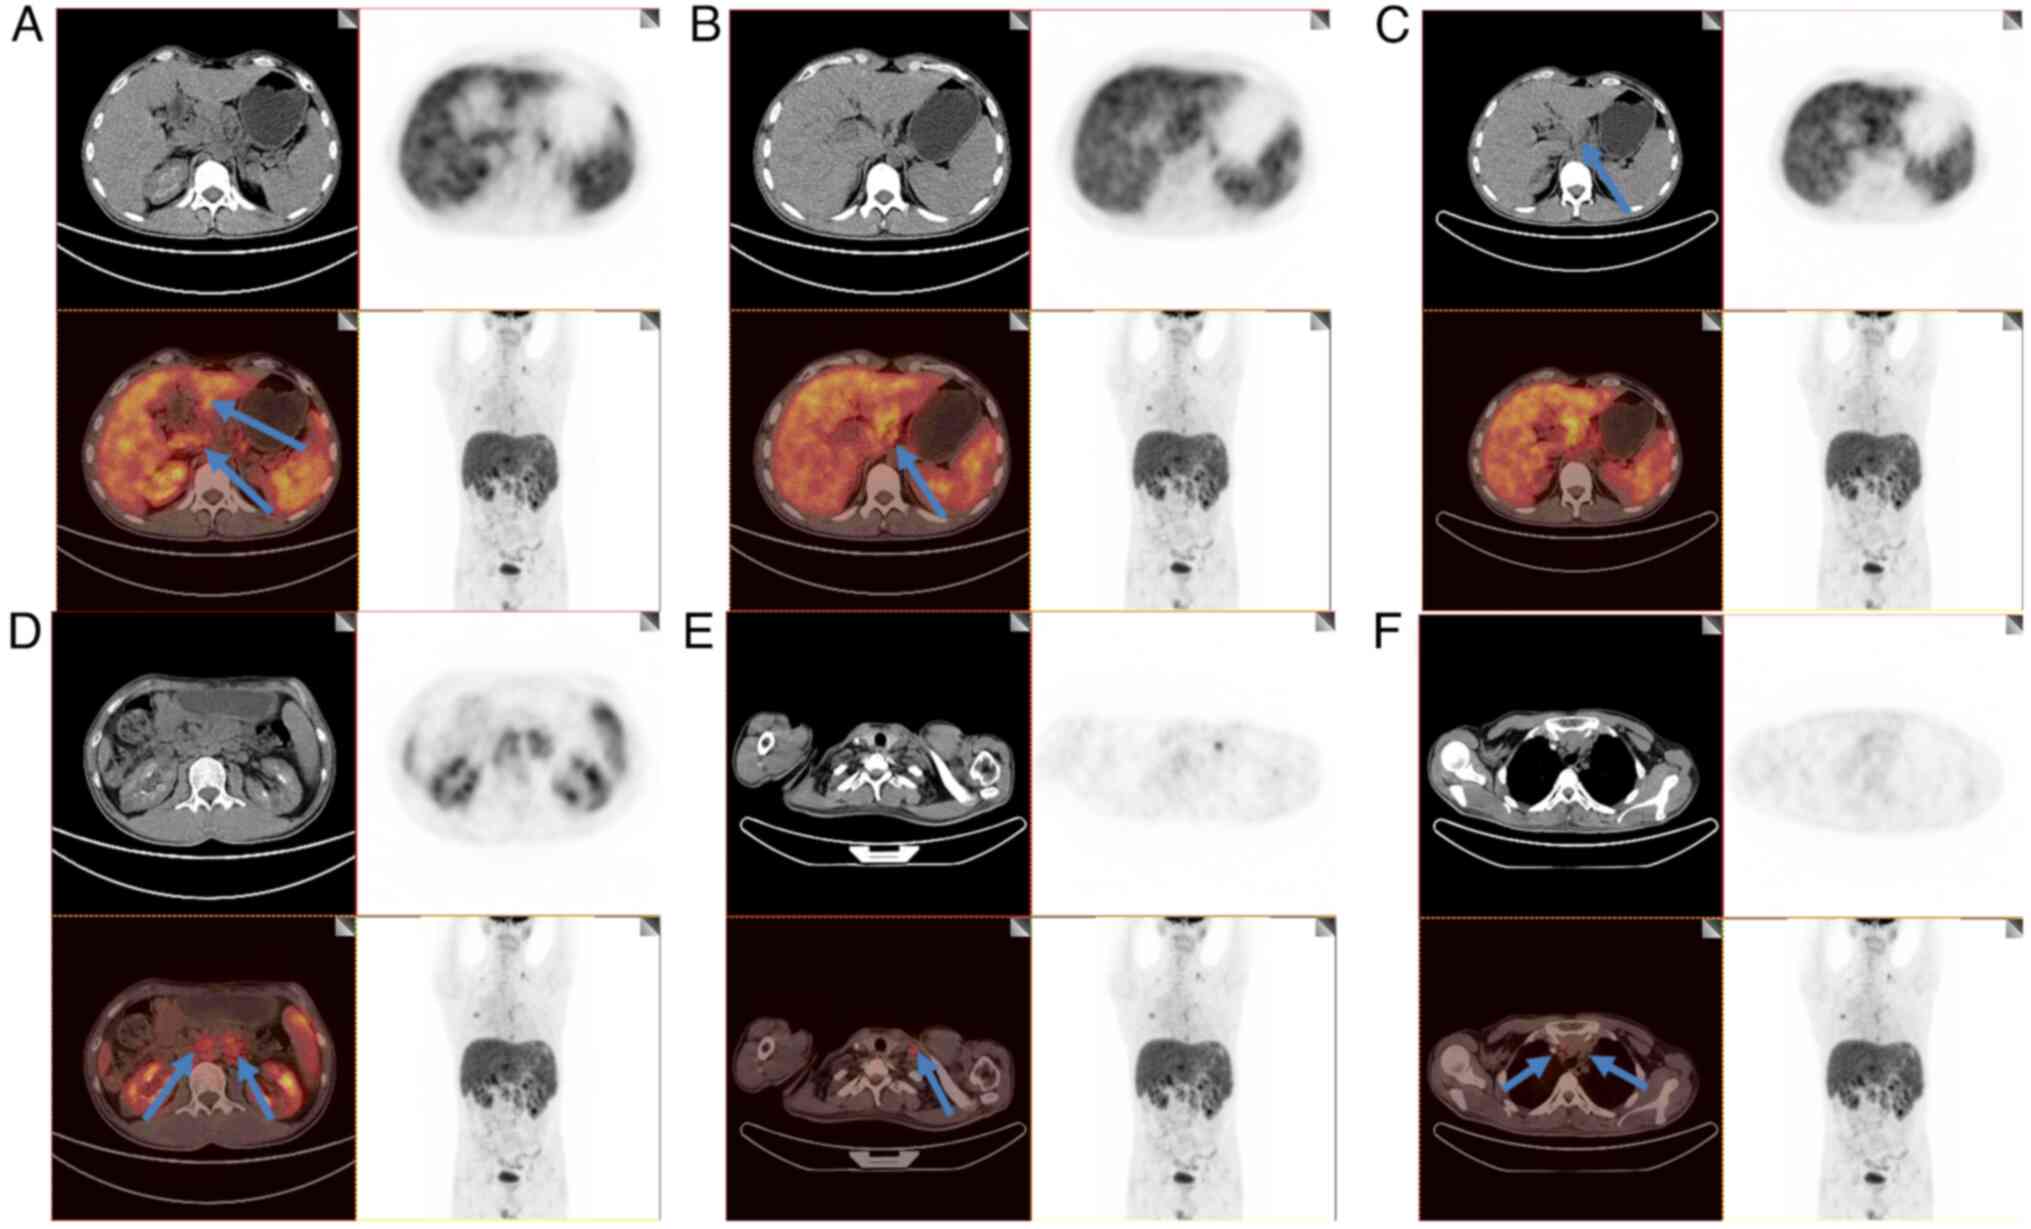

Deep lymph node enlargement and renal failure caused by hypercalcemia‑associated sarcoidosis: A case report

Sarcoidosis is a rare disease that severely affects the lungs and superficial lymph nodes. In addition, this disease can also affect the skin, eyes and kidneys to varying degrees. The present report described a 32‑year‑old male patient who was admitted to Renmin Hospital of Wuhan University (Wuhan, China) due to joint pain in the extremities. He was diagnosed with uncorrectable hypercalcemia. A lymph node biopsy revealed the hypercalcemia to be associated with sarcoidosis, with the patient also demonstrating renal failure and lymph node enlargement. Administration of glucocorticoids provided benefits in terms of both primary and recurrent sarcoidosis, which also improved and preserved renal function. After being prescribed with oral prednisone treatment, blood calcium levels returned to normal, which indicated markedly improving renal function. However, the discontinuation of glucocorticoids for 2 months resulted in increased serum calcium and creatinine levels, both of which returned to abnormal levels. Overall, the present case report suggests that clinicians should actively perform sarcoidosis treatment in clinical practice to overcome any unexpected results associated with organ damage.

Figure 4

Figure 5